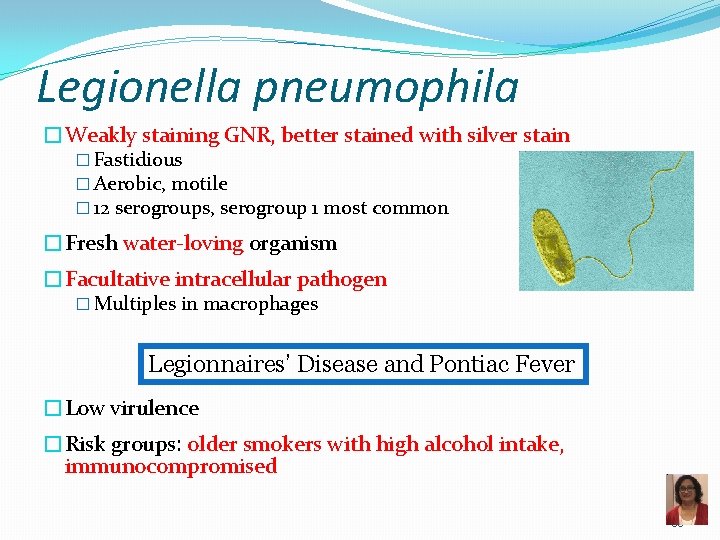

Legionella pneumophila �Weakly staining GNR, better stained with silver stain � Fastidious � Aerobic, motile � 12 serogroups, serogroup 1 most common �Fresh water-loving organism �Facultative intracellular pathogen � Multiples in macrophages Legionnaires’ Disease and Pontiac Fever �Low virulence �Risk groups: older smokers with high alcohol intake, immunocompromised 95